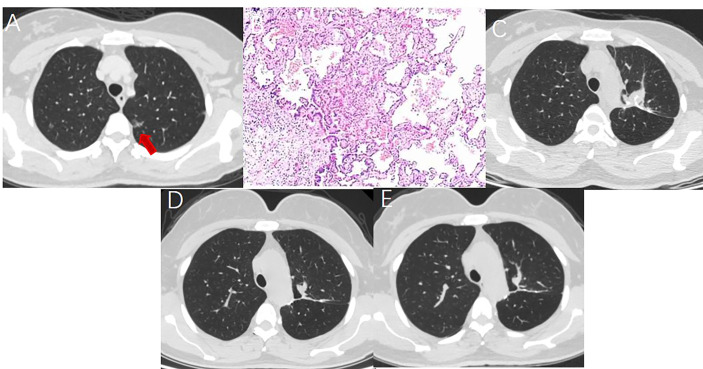

Figure 2.

A 52 year-old woman with multiple GGNs underwent resection of apical posterior segment of left upper lobe and lymph node sampling. (A) A ground glass nodule with a diameter of 1.5cm located in the left upper lobe. (B) Postoperative pathology showed minimal invasive adenocarcinoma with no lymph node metastasis. (C) Soft tissue-density mass and linear stapler can be seen in the operation area on the CT image one month after surgery. (D) The soft tissue density mass in the operation area shrank 7 months after surgery. (E) The operation area formed fibrous scar 14 months after surgery.